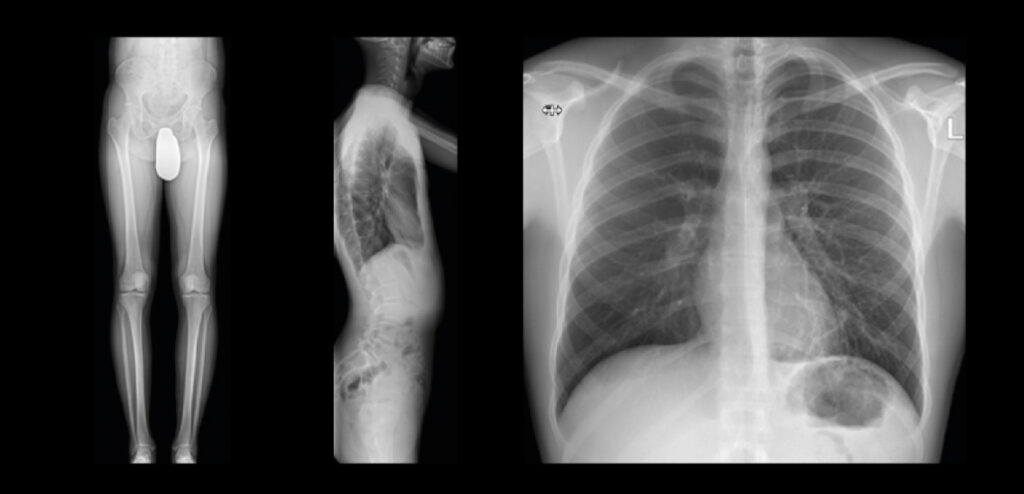

Le applicazioni speciali e DiamondView MAX

aiutano a mantenere la dose più bassa possibile, mentre è possibile vedere tutti i dettagli anatomici in immagini chiare per prendere decisioni diagnostiche sicure per tutti i pazienti.

Image stitching preciso con Smart Ortho1

Immagini senza griglia

DiamondView MAX è stato sviluppato specificamente per offrire una qualità dell’immagine ottimizzata per esposizioni senza griglia